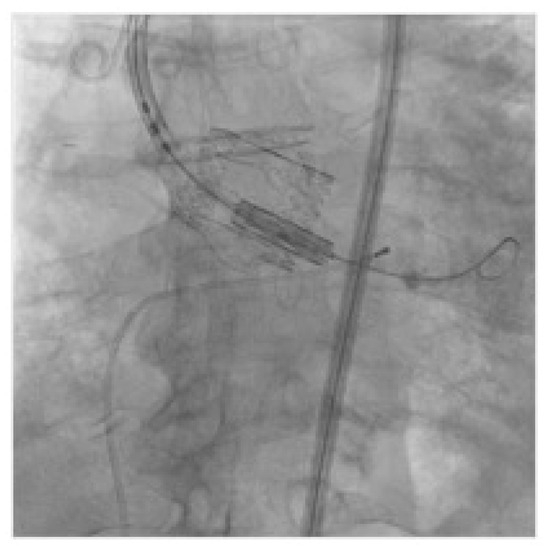

2.2. Technology

2.3. VIV-TAVR Planning and Technical Procedures